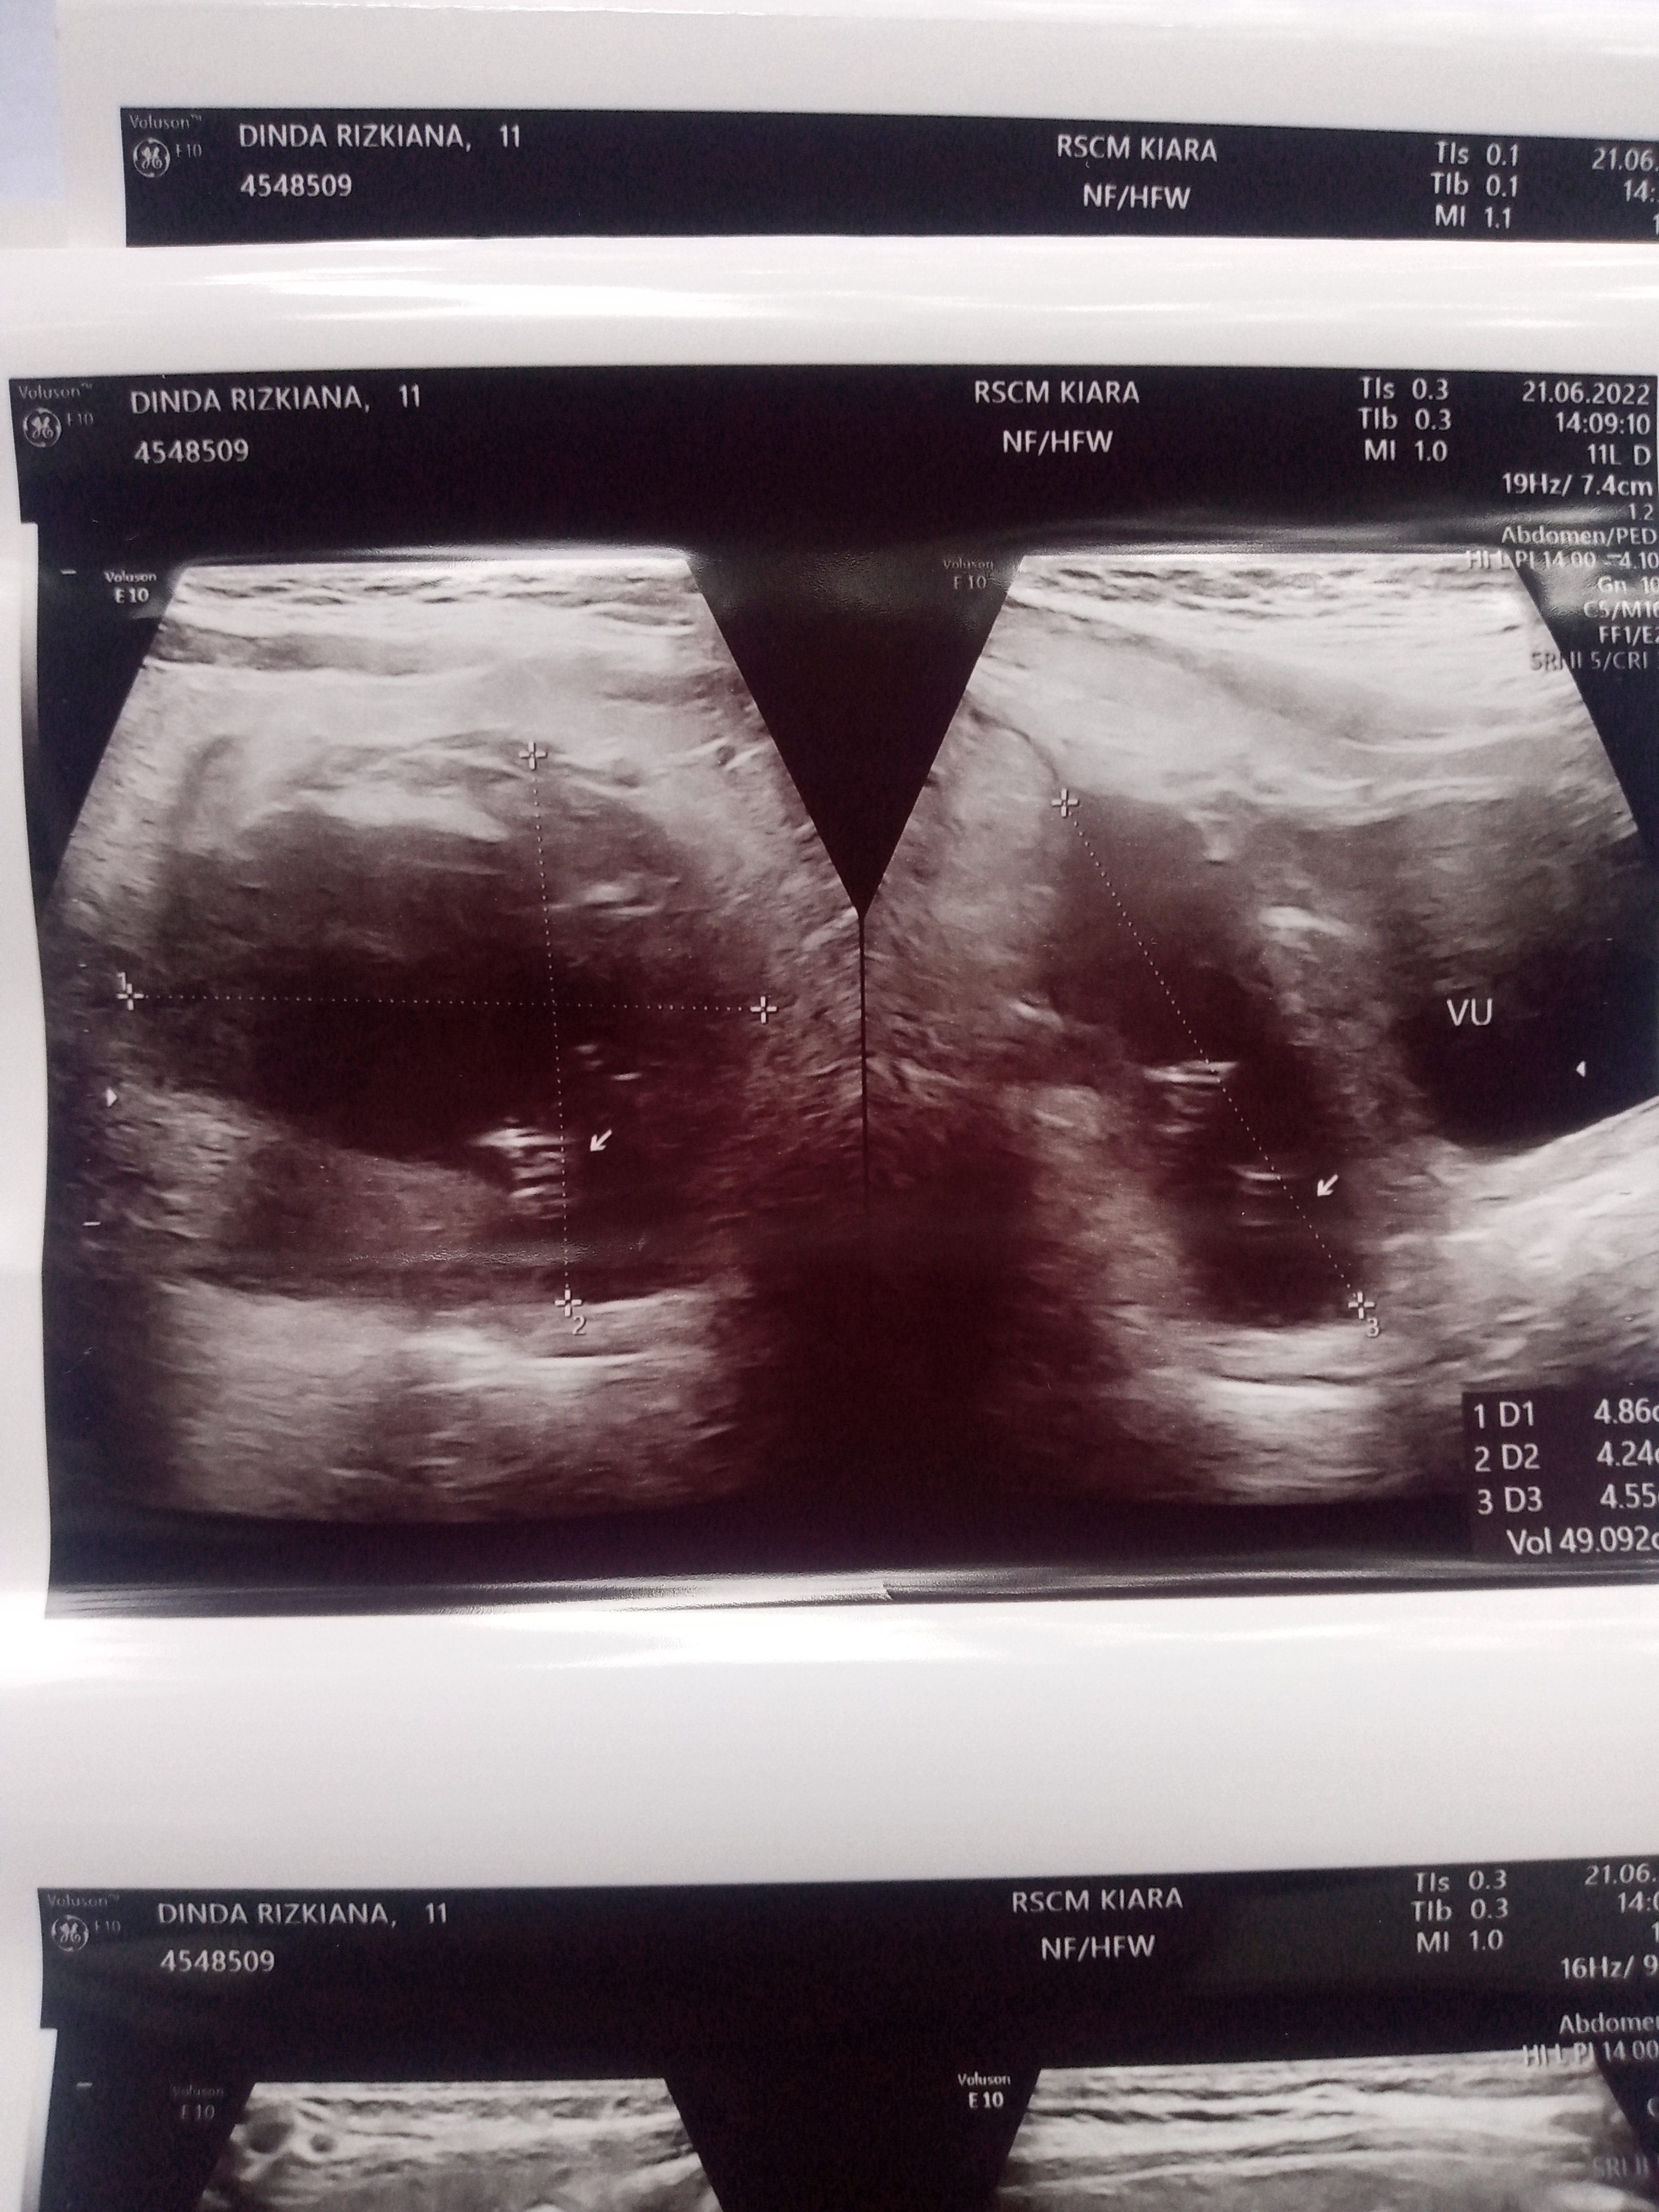

Pada tgl 21 Juni 2022 Telah dilakukan USG Abdomen di Dept IKA RSCM Kiara, dengan hasil sebagai berikut:

Hati tidak membesar, parenkim homogen, permukaan rata, tepi kaudal Lancip, sistern vaskuler biller tidak  melebar; tidak tampak kelainan.Kandung empedu tidak tampak kelainan.    Limpa tidak membesar, parenkim homogen, tidak tampak kelainan.Ginjal kanan dan kiri tampak jeias, ekoparenkim meningkat dibandingkan hati dan Limpa, diferensiasi    korteks dan medulla masih jelas. sistem pelviokalises tidak melebar. Ginjal kanan ukuran 7,74 crn, kiri  ukuran 8,7 cm (normal.: 8,2 - 11 cm).    Kandung kemih terisi urin, dinding tidak menebal, tidak tampak internal echo di dalamnya.    Tampak cairan intraabdomen dengan internal echo    Tampak kateter tenckhoff dari abdomen kiri dengan tip proyeksi pelvis minor. Pada tunnel subkutan dan intraabdomen tampak lesi hiperekoik dengan gambaran anekoik di sekitarnya. Pada ujung tip tenckhoff  etrovesika) tampak lesi hipoekoik berbentuk kantung dengan dinding tipis dengan estimasi volume 49ml, tampak internal echo di dalamnya.

Peritoneum/mesenterium tampak menebal dan ekogenik.  Tampak lesi hipoekoik berdinding tebal di jaringan lunak regio    dengan internal echo didalamnya berukuran 2,S x 1 x 2,5 cm_ Pada colour flow tampak vaskularisasi perifer. Tampak pula lesi  hipoekoik 2 jari keatas    berbentuk bulat, berbatas tegas, berukuran 0.„26 x 0,12 x 0,27 cm, tidakt ampak hubungannva dengan intra abdomen ataupun kutis (ex exit site),    Tidak tampak massa intra abdomen.

Kesan:

Uremic kidney  bilateral.

Peritonitis

Ascites kompleks

Abses regio umbilikal

Fokus infeksi sekitar tunnel tenckhoff

Pocket abses pada tip tenckhoff

Informasi dari dr Eka Laksmi spA (K) selaku DPJP dari hasil USG abdomen dan Hasil Cek Lab Darah dan sudah dikonsul kan ke Dept Urologi RSCM bahwa in syaa Allah Dinda Rizkiana Keysha akan menjalani Operasi Pelepasan Selang CAPD dengan jadwal hari Senin tgl 27 Juni 2022.